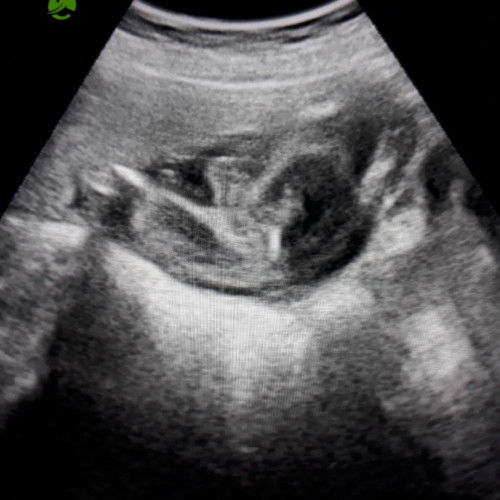

22 weeks trans abdominal ultrasound

Hello mga mie, ito po result sa trans abdominal ultrasound ko kanina. 22 weeks at 80% boy daw po. May chance po ba na mabago pa yun? at boy po ba talaga? sino po dito may alam ano basihan na boy po? sabi kasi ng doctor kanina baka sa pusod lang daw nya po yung nakita na pototoy. Ps. no to bash po sana, gusto ko lang po magtanong.

baka po kasi may obstruction sa imaging, pero kitang kita napo yung gender pag 22 weeks, di na po yun nababago. unless di sure yung OB and yung pag check po ng gender is either na shy baby nyo po like tinago nya yung part na yun and di maka kuha ng clear result yung OB

mas accurate Pag magpa 3D or 4D or CAS, mostly kac Pag utz lng 2 dimensions lng kac makikita kaya d rin sigurado depende din sa position ni baby.